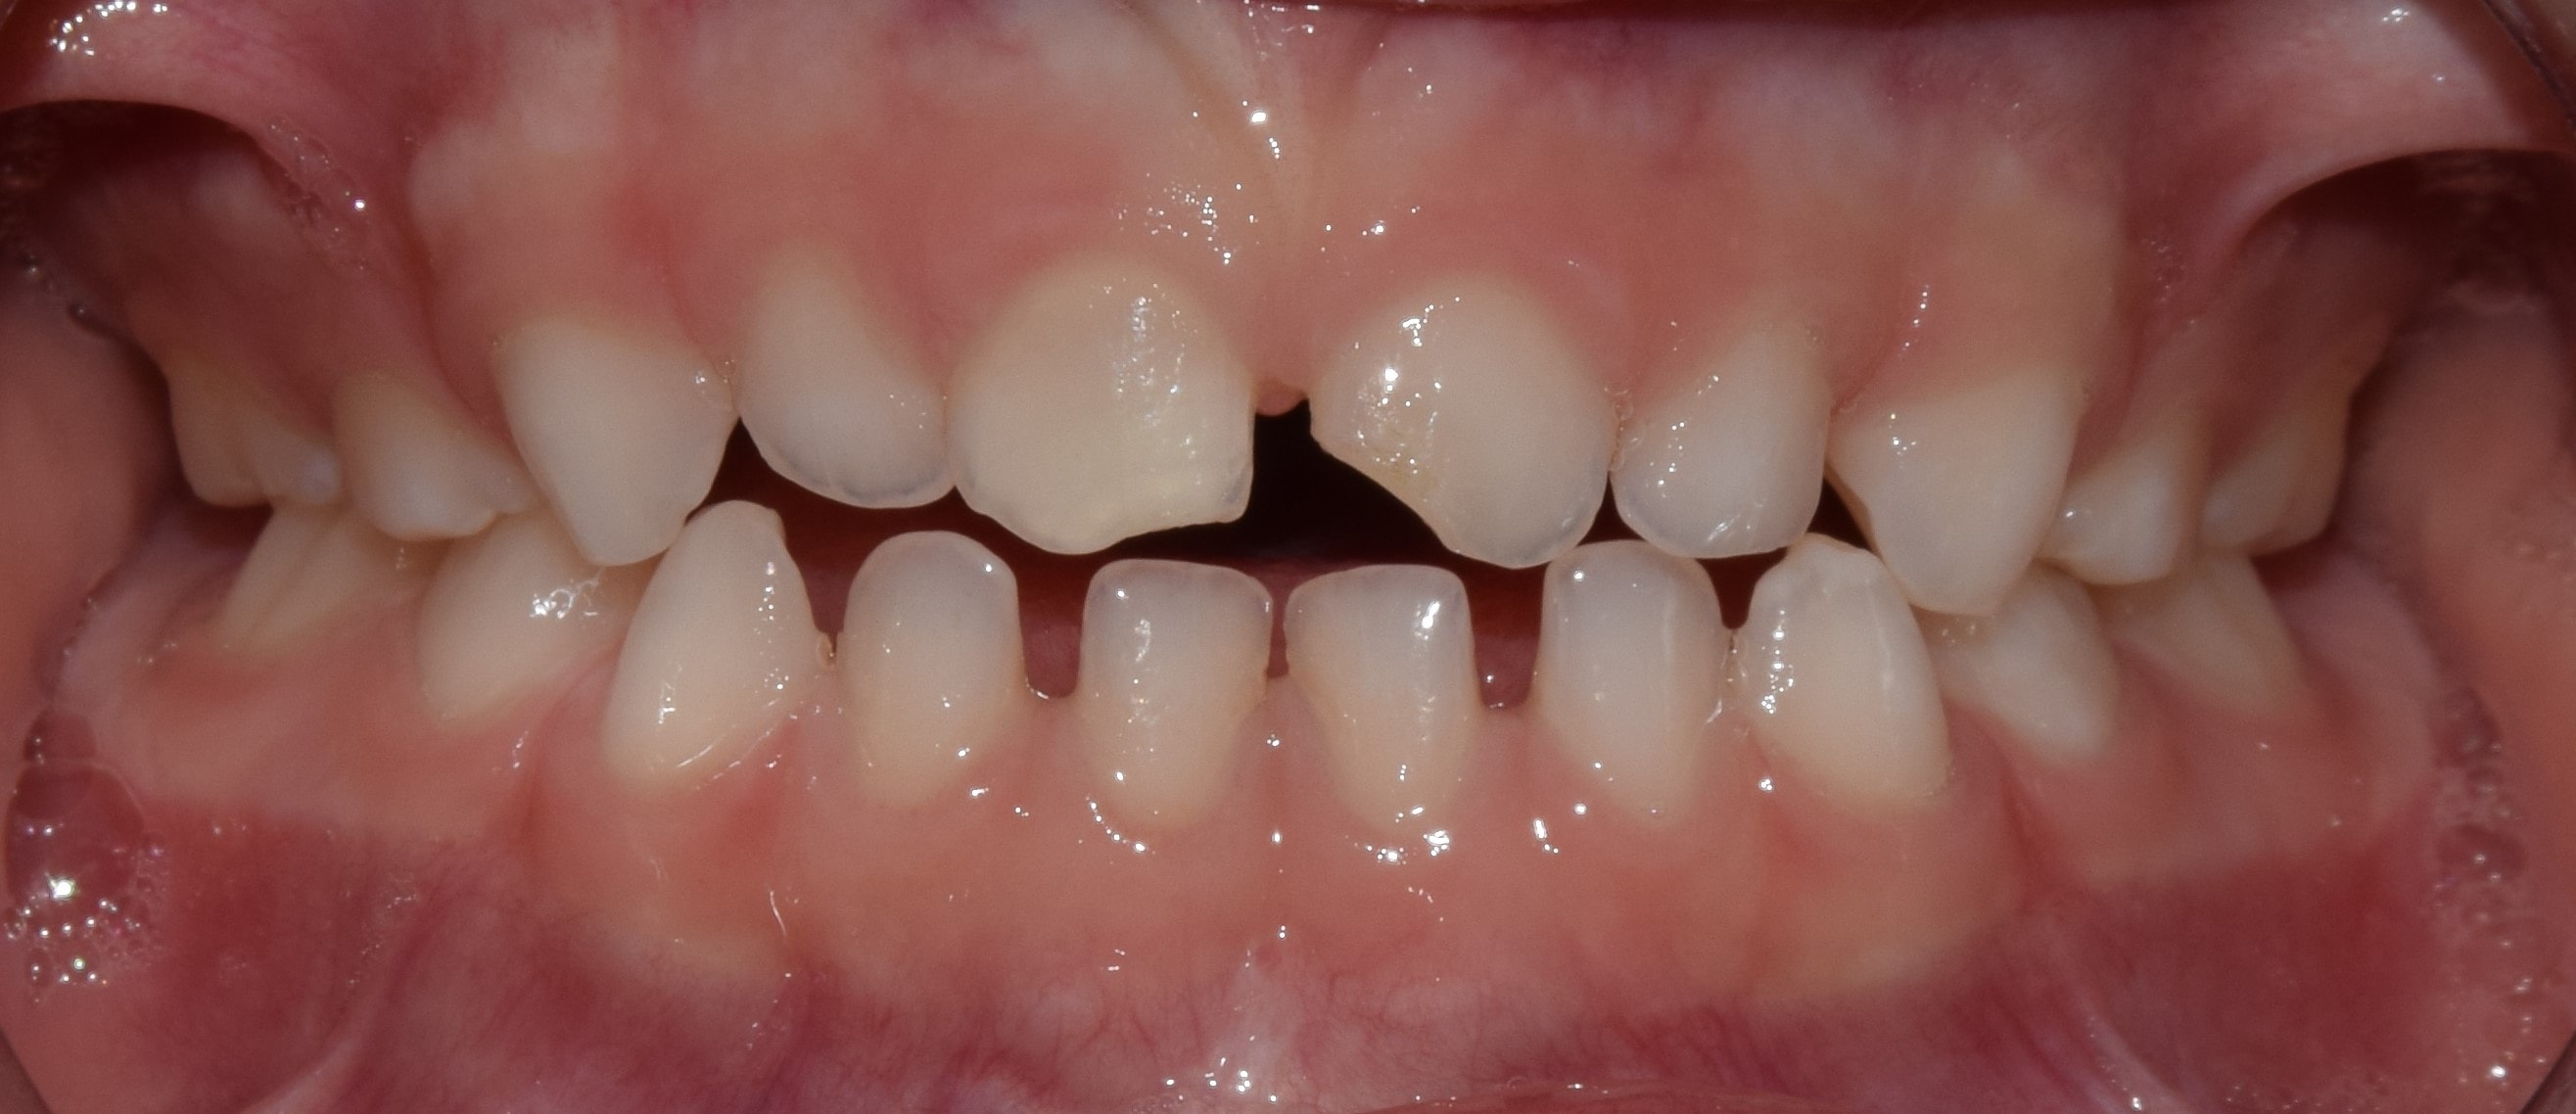

Korai vegyesfogazat

7-8 éves kor körül a gyermekek többségének korai vegyesfogazata van. Ez azt jelenti, hogy az első maradó nagyőrlők előtörtek, a tej metszőfogakat pedig felváltották a maradó metszőfogak.

Késői vegyesfogazat

10-11 éves korban beszélünk késői vegyesfogazatról, amikor megkezdődik az oldalsó tejfogak elvesztése, és a tej őrlők, tejszemfogak helyére nőnek a maradó kisőrlők és szemfogak. Késői vegyesfogazatban a szájüregben eltérő sorrendben nőnek a maradófogak, illetve esnek ki a tejfogak.